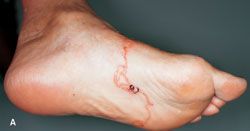

A linear, severely pruritic rash erupted on the lateral and plantar aspects of the left foot of a 72-year-old woman who had recently been camping on a Caribbean beach. Antihistamines and locally applied antifungal agents offered no relief.

Answer: Cutaneous Larva Migrans